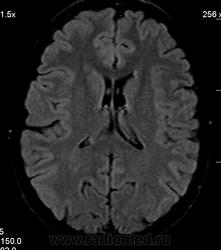

Можно ли  трактовать участок повышенного МР-сигнала по Т2 в правой лобной доле как участок перивентрикулярного глиоза?

Часто встречаемая структура, не задумывался что "это" конкретно, наверное Робин-Вирховские. В данном случае - изменения по-моему просто несколько асимметричны.

Большое спасибо. Да, симметричная линейная паравентрикулярная структура в области передних рогов встречается часто, на что обычно не обращаю внимания. В этом случае смутила ее асимметричность (особенно на Coг. срезах), если думать что это Вирхова-Робина, то возможно это слабо выраженный периваскулярный глиоз.

Иногда у пациентов с дисциркулятонной энцефалопатией по периферии расширенных периваскулярных пространств встречала линейное повышение нтенсивности МР-сигнала на Tirm, расценивала как периваскулярый глиоз, и у нескольких пациентов перенесших перинатальную энцефалопатию видела относительно симметричные зоны паравентрикулярного глиоза резидуального характера в области задних и иногда передних рогов. Поэтому и задумалась, увидив такую асимметричность интенсивности сигнала в этом случае, заподозрив "нерезко выраженный" глиоз справа.

1) господа МРТшники, если это расширенное вирхов-робиновское пространство, как вы объясните тот факт, что в TIRM последовательности сигнал от данного участка высокий?

2) данная находка (единичный мелкий дисциркуляторный очаг) имеет мало практической ценности. не описали бы - ничего страшного. такие перивентрикулярные изменения бывают у очень многих людей и тяготеют к норме для тех, кто старше 40 лет.

3) термин "глиоз" - гистологический, и применять его в лучевой диагностике некорректно, ИМХО.  в дисциркуляторных очагах помимо глиоза находят и другие изменения.